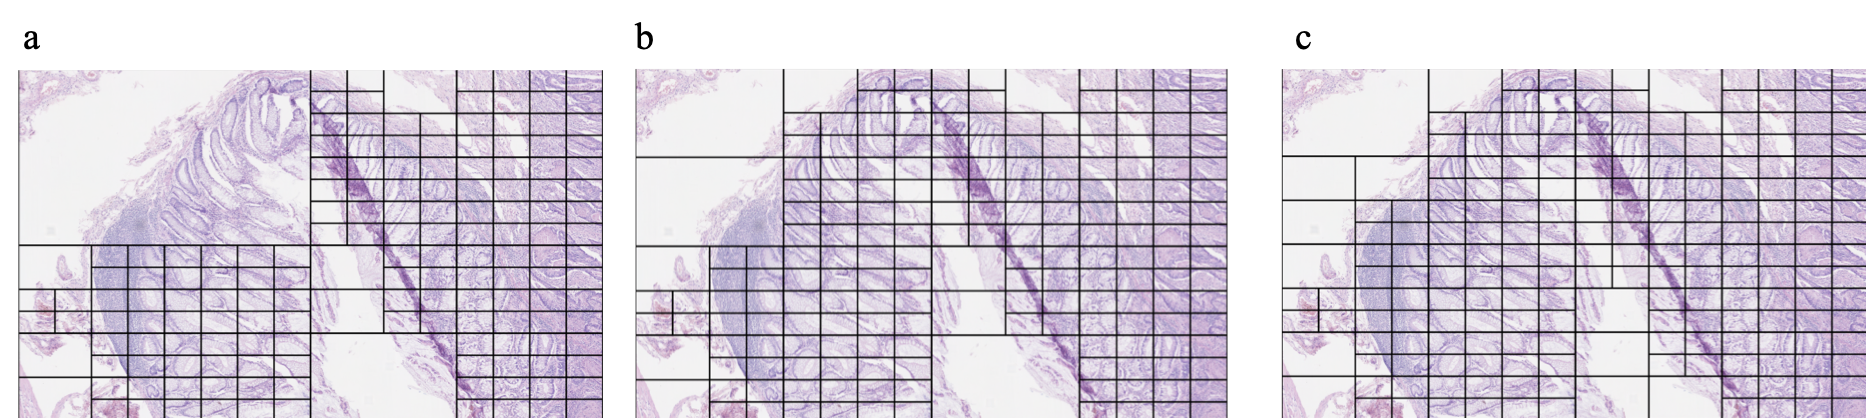

Refer to caption

Figure 2: Example of quadtree decompositions in different colour spaces. a Image decomposed using entropy in RGB space. b Image decomposed using mean pixel value in blue ratio space. c Image decomposed using mean pixel value of haematoxylin channel. The splitting threshold was set to the mean (μ𝜇\mu) minus one standard deviation (σ𝜎\sigma) for each case.

We found that the mean pixel value in the Haematoxylin channel gave the best qualitative decomposition of the input images. Figure 2 shows an example of this. The method consistently split the image into finer grained detail in the presence of tissue while ignoring the background or less informative regions such as empty space or large areas of adipose tissue. Furthermore, it would aggressively split regions in the presence of cancerous tissue while with non cancerous tissue the method would sometimes only split down to a depth of 2 or 3 in more homogeneous areas such as large regions of connective tissue. This was not found to be the case in large regions of cancerous tissue where the method would consistently split the image down to the maximum allowed depth. Additionally, the threshold of μσ𝜇𝜎\mu-\sigma was empirically found to give the best qualitative splits by consistently following and splitting the tissue regions within the images.